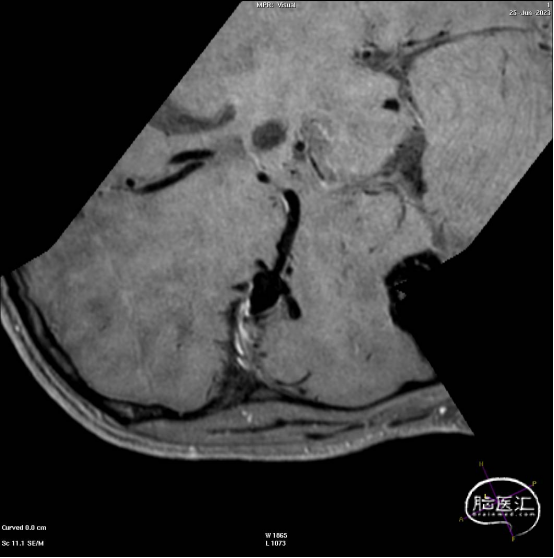

此为左侧大脑中动脉瘤,近端血管极为迂曲,瘤体有突出的子囊,动脉瘤与载瘤动脉有一定夹角,动脉瘤呈上窄下宽形状,M2段下干从瘤颈近端发出。

动脉瘤平均宽度5.41mm, 最小高度为3.71mm,瘤颈约为4.94mm,使用WEB™ SL 6*3mm瘤内扰流装置进行栓塞治疗。

释放WEB™:缓慢推出WEB™从种子至萌芽状态,继续向瘤腔内远端缓慢推送WEB™至萌芽至开花间状态;将WEB™和VIA™送至瘤顶,固定WEB™推送杆回撤VIA™,WEB™完全释放。

经造影可见WEB™尺寸合适,贴合瘤壁,覆盖瘤颈,且下支M2段分支及其他分支血管血流通畅。

解脱后,再次造影和Dyna-CT评估,可见动脉瘤瘤腔内有明显造影剂滞留,分支血管血流正常。

大脑中动脉瘤充分栓塞,瘤颈残留,WEB™充分栓塞。WEB™被压缩且位置偏转,分支血管有影响。